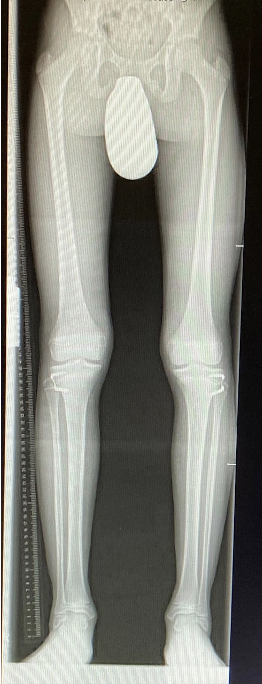

Wachstumslenkung mit moderner Klammer oder eight plate

Bei offenen Wachstumsfugen kann über eine Steuerung des Wachstums mit einer Klammer (Blount-Klammer/Flex Tack) oder kleinen Plättchen (Eight Plate) eine Korrektur von Achsabweichungen in der sagittalen und coronaren Ebene erreicht werden (Abb. 8). Der Hautschnitt beträgt ca. 1,5 - 2 cm und die so versorgten Kinder können ihre Extremität direkt postoperativ schmerzadaptiert voll belasten. Die wachstumslenkende Operation mit einer Klammer oder einem Plättchen besitzt ein enormes Korrekturpotential und erspart dem Kind oder Jugendlichen umfangreiche Umstellungsosteotomien und Plattenosteosynthesen, welche eine Schnittlänge von 15 cm und eine Entlastung des operierten Beines von 4-6 Wochen erforderlich machen.

Abb. 8 a-g: Genua vara prä- und postoperativ versorgt mit Flex Tacks (a-b) und ein Genu valgum versorgt mit Eight Plate an der medialen Femurkondyle (c); Spitzfuß bei congenitalem Klumpfuß und einem Flat Top Talus mit präoperativem Röntgenbild seitlich und der deutlich nach dorsal stehender Tibia(d); intraoperative Bilder der Epiphysiodese mittels Eight Plate zur Wachstumslenkung der distalen Tibia in die Extension (e-f) und postoperativer Verlauf nach sechs Monaten mit regelrecht stehender Tibia über dem Talus durch die distale Extension (g).